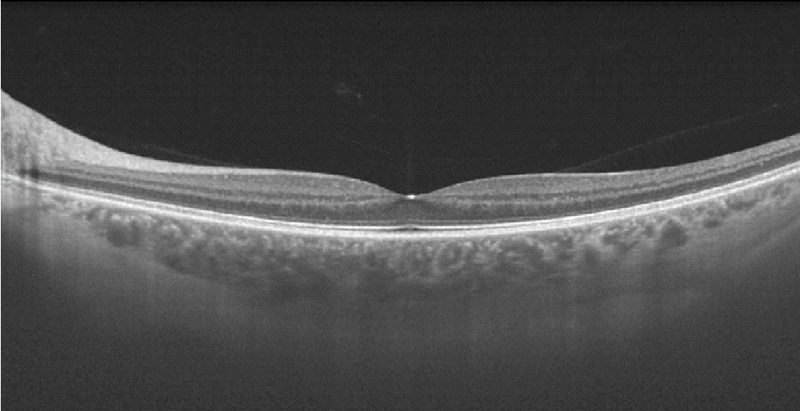

En la imagen superior de la

Figura 1 puede verse una OCT macular realizada con HD- OCT (Cirrus de Zeiss) aumentada, y en la imagen inferior realizada con OCT de última generación DRI-OCT (Atlantis de Topcon).

Figura 1. OCT en voluntarios sanos. Imagen superior: OCT realizada con HD-OCT (Cirrus de Zeiss); imagen inferior: OCT realizada con tecnología DRI-OCT (Atlantis de Topcon). En ambas imágenes pueden distinguirse las cuatro líneas hiperreflectivas de la retina externa (desde la parte vítrea o más interna a la parte coroidea o más externa): membrana limitante externa (MLE), zona de los elipsoides (EZ), zona de interdigitación (IZ) y complejo EPR-membrana de Bruch.